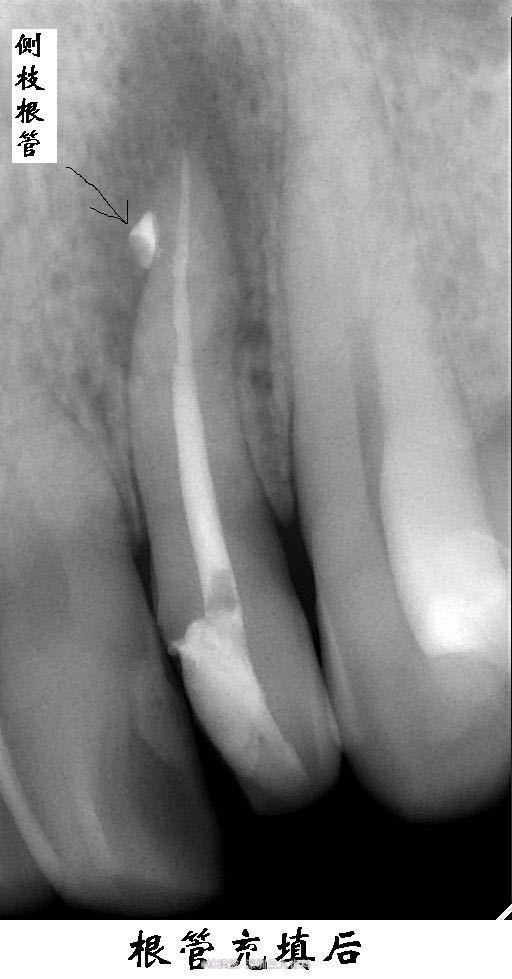

左上侧切牙侧枝根管一例

22近中龋及髓,冷(+)。

诊断:22牙髓炎 处理:22根管治疗

侧枝根管治疗